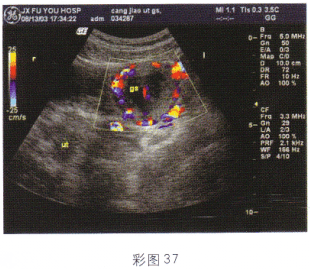

4.女性,27歲,停經48天,陰道不規則出血6天;血HCG70μg/ml。結合超聲圖像(彩圖37),最可能的診斷是

A.卵巢畸胎瘤

B.附件炎性包塊

C.子宮漿膜下肌瘤

D.異位妊娠

E.卵巢囊腺瘤

正確答案:D解題思路:附件區見囊實混合性光團,邊界尚清晰,子宮腔內有分離?;颊哂型=?,不規則陰道出血,且血HCG增高。